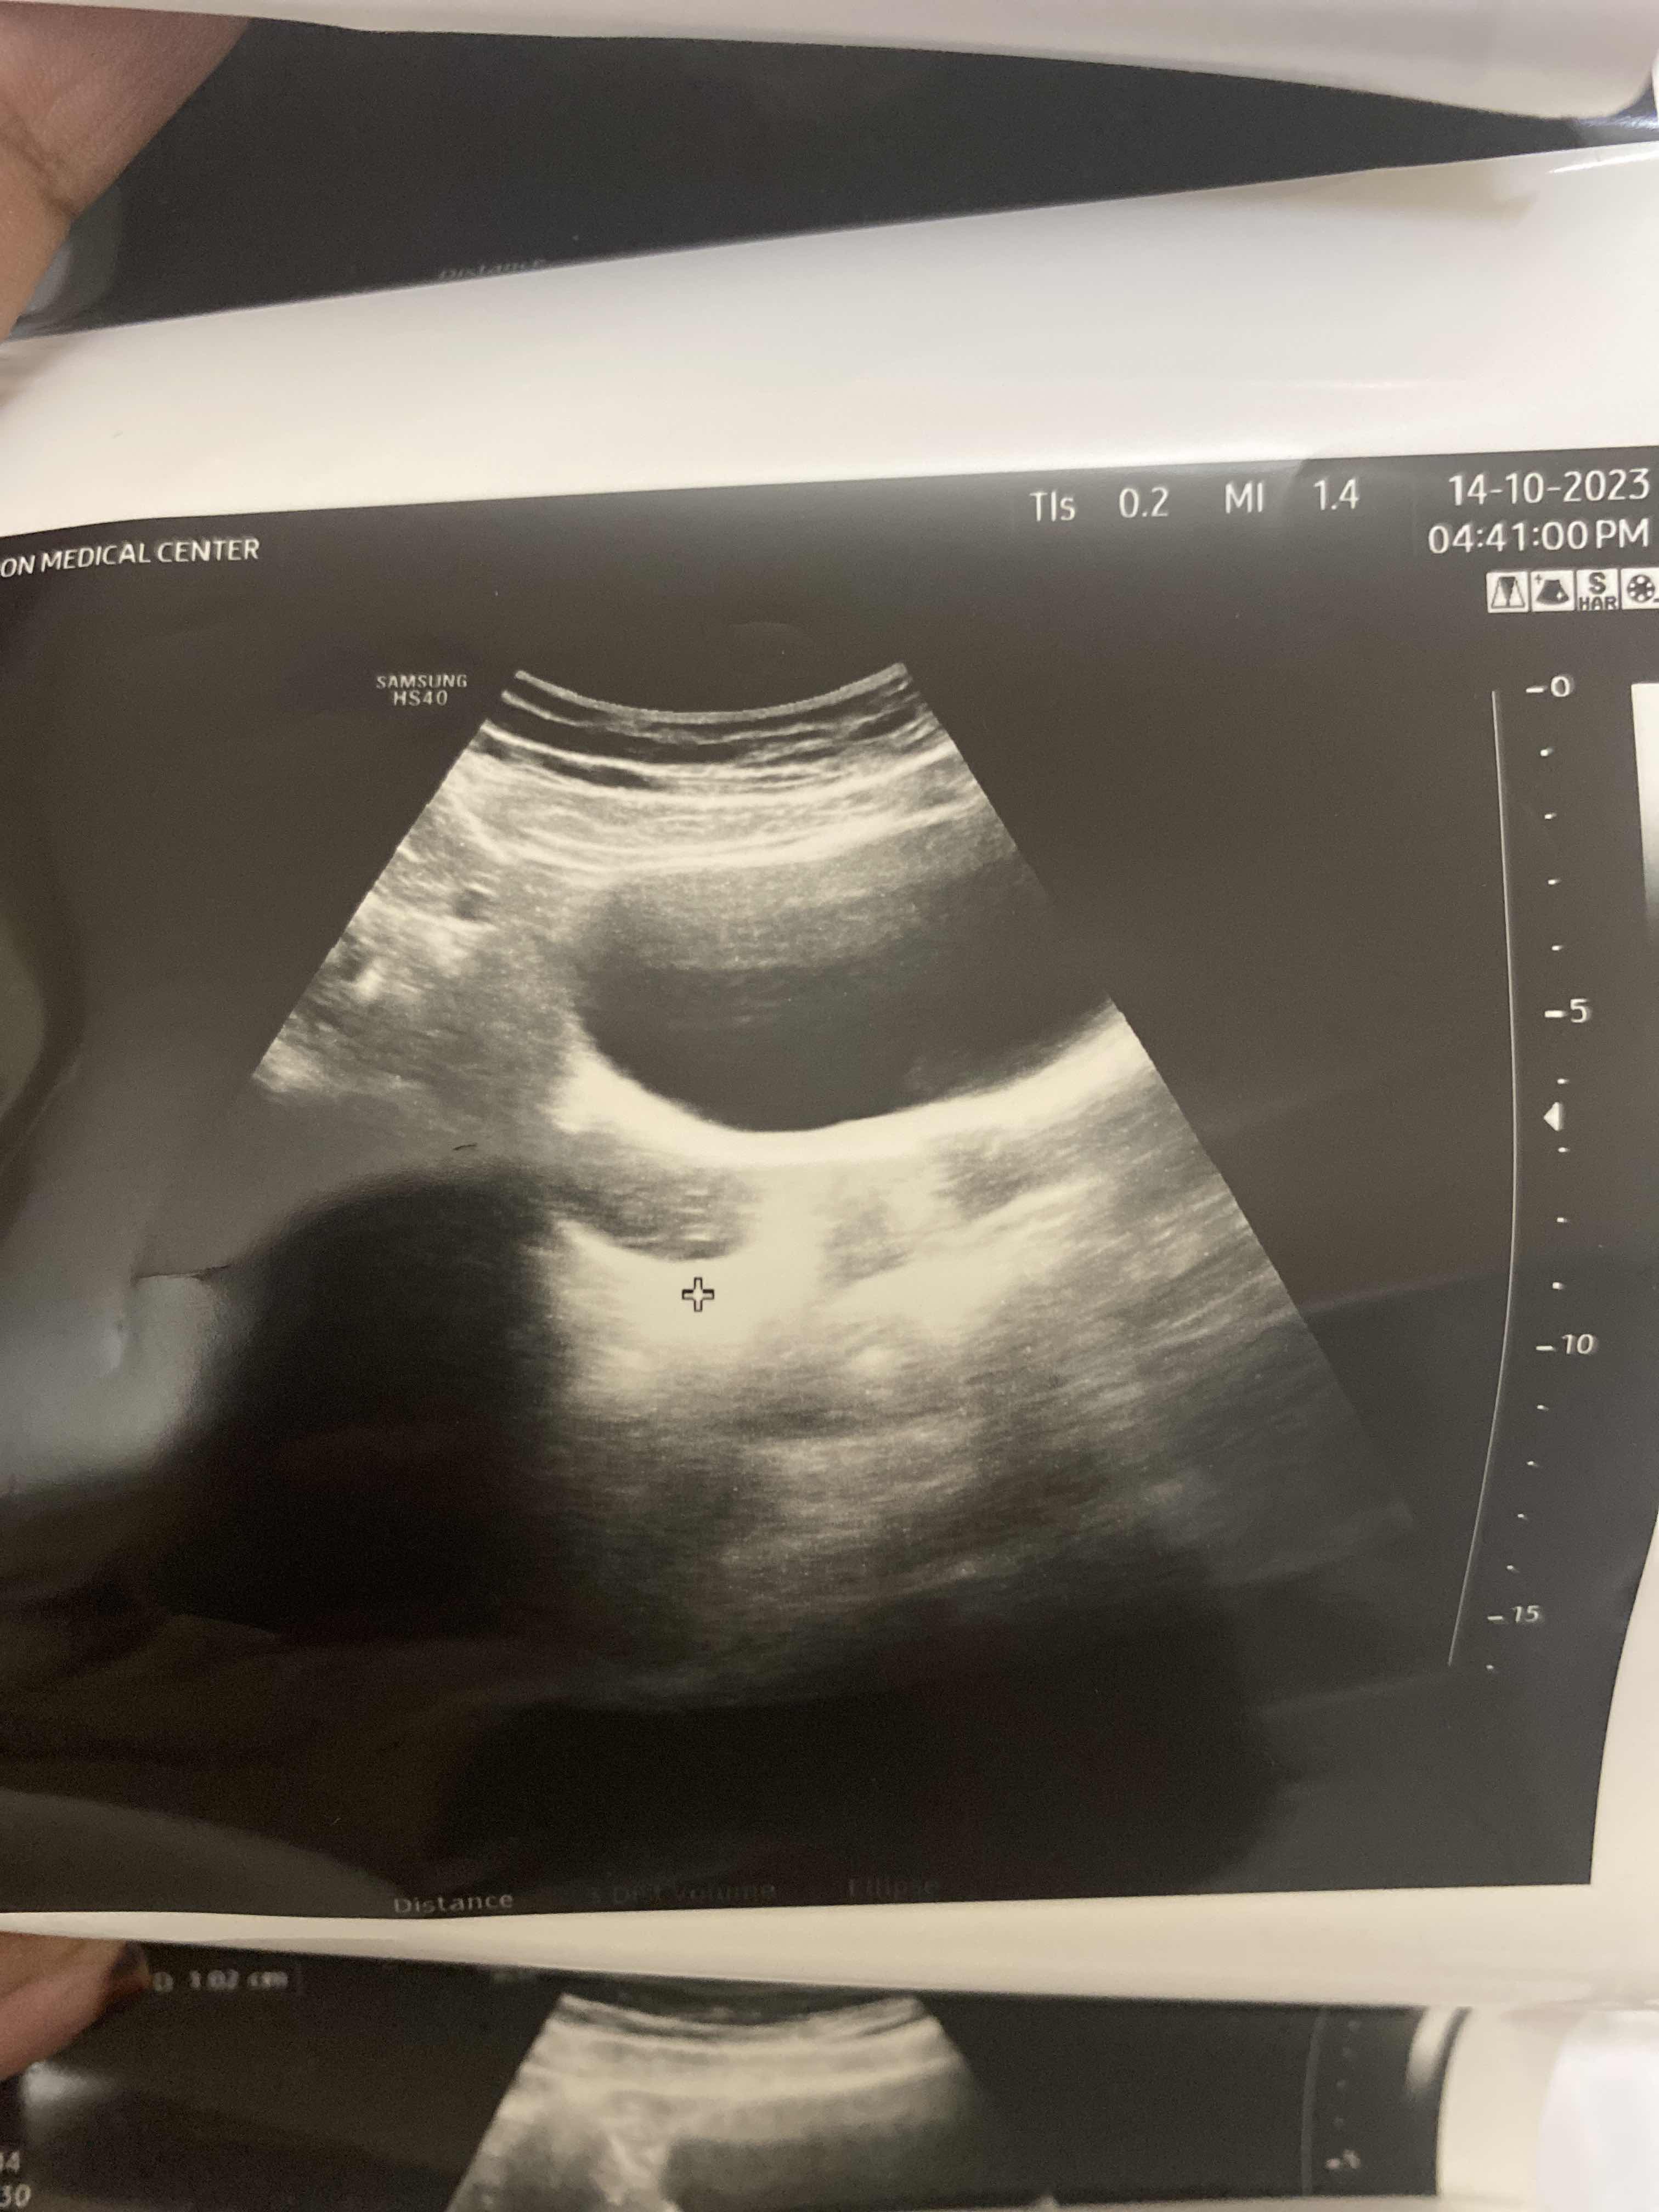

هذي صورة الالترا ساوند لتكييس كنت ابي اعرف حجمه هل هو كبير او صغبر و الدكتوره اعطتني prox-fem اذا انقصت...